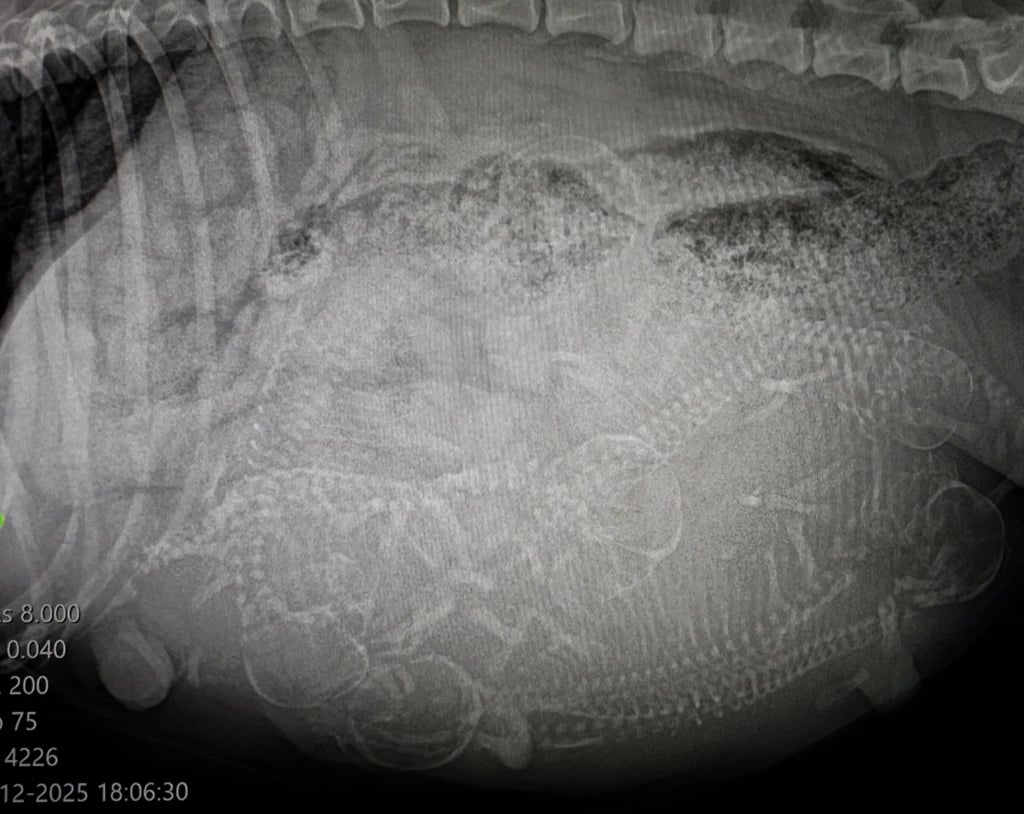

Radiografia: quanti cuccioli ci aspettano?

Ieri abbiamo effettuato la radiografia alla nostra cagnolina e sono risultati 5 cuccioli, con la possibilità di un sesto cucciolo ancora da confermare. Dall’ecografia abbiamo potuto vedere che tutti i cuccioli stanno bene e stanno crescendo regolarmente.